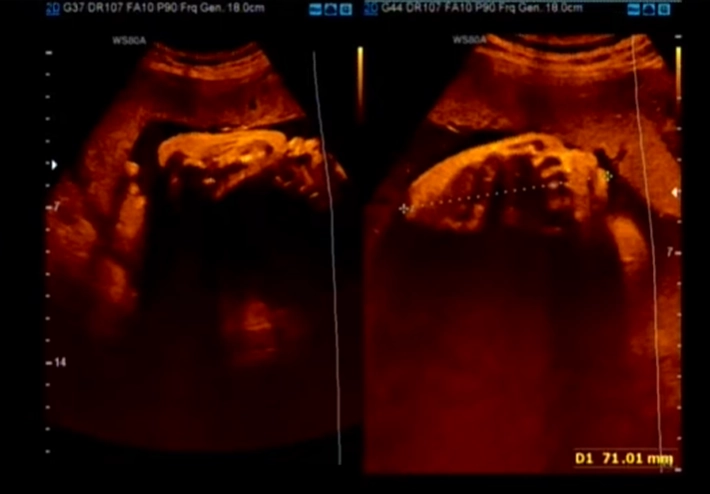

• XII. Hệ cơ xương khớp thai nhi

• Giải phẫu siêu âm cơ xương khớp quý I

• Loạn sản xương quý I (Skeletal dysplasias)

• Cơ xương khớp thai

• Tổng quan CXK

• Tổng quan cơ xương khớp thai nhi (Approach to fetal skeletal)

• Chẩn đoán phân biệt

• Ngắn nhẹ xương đùi / xương cánh tay thai (Mildly Short Femur / Humerus)

• Xương cong ở thai nhi (Curved / Angulated Bones)

• Bất thường cốt hóa thai (Abnormal Ossification)